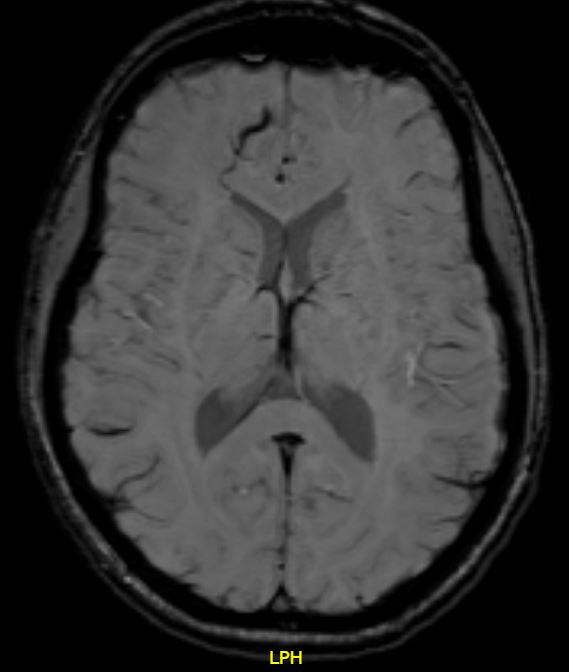

In this instance version of the head to the one side at the start of a seizure is reliably indicative of contralateral frontal involvement. This is not to say that the seizure started on the frontal lobe, but the retained awareness indicates that the seizure is still relatively spatially restricted, even if it has propagated from insular cortex or frontal or temporal operculum. The EEG demonstrated no spikes, while the MRI demonstrates evidence of a right frontal developmental venous anomaly. These are relatively common coincidentalomas; I have yet to see one associated with the region of seizure onset (symptomatology and electrophysiology have always indicated otherwise), but this one may be causally related. There is precedent for this, albeit rare.

MRI